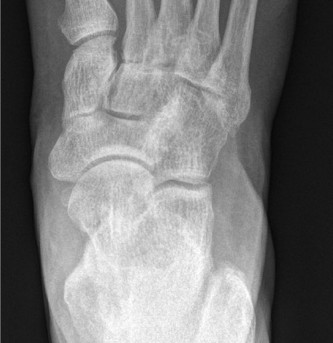

Radiographic evaluation must include weight-bearing anteroposterior (AP), lateral, and oblique views of the foot. On the AP view, the congruency of the medial border of the second metatarsal with the medial border of the middle cuneiform is assessed. On the lateral view, the Meary's angle (the angle between the long axis of the talus and the first metatarsal) is evaluated to quantify sagittal plane collapse. In complex deformities or post-traumatic settings, a non-contrast Computed Tomography (CT) scan is mandatory to map the extent of joint destruction, assess bone stock for hardware purchase, and evaluate for subchondral cysts or avascular necrosis of the navicular.